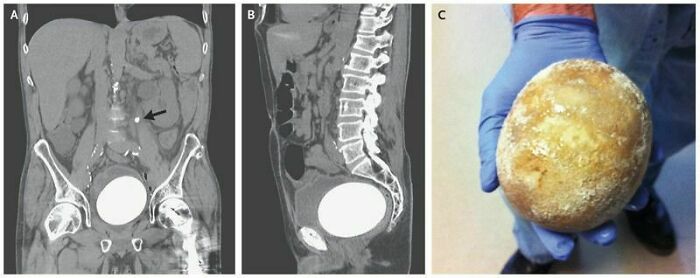

#37 Neobladder Stone

Image source: Surgeox

#24 My Husband Suffers Frequent Kidney Stones. He Just Passed This Nightmarish Thing

Image source: MangoyWoman